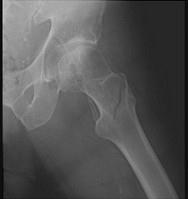

股骨转子间骨折(如图)容易发生的并发症是 ( )A、创伤性髋关节炎B、股骨头缺血性坏死C、损伤性骨化D、髋内翻畸形E、骨折不愈合

问题 股骨转子间骨折(如图)容易发生的并发症是 ( )

选项 A、创伤性髋关节炎 B、股骨头缺血性坏死 C、损伤性骨化 D、髋内翻畸形 E、骨折不愈合

答案 D